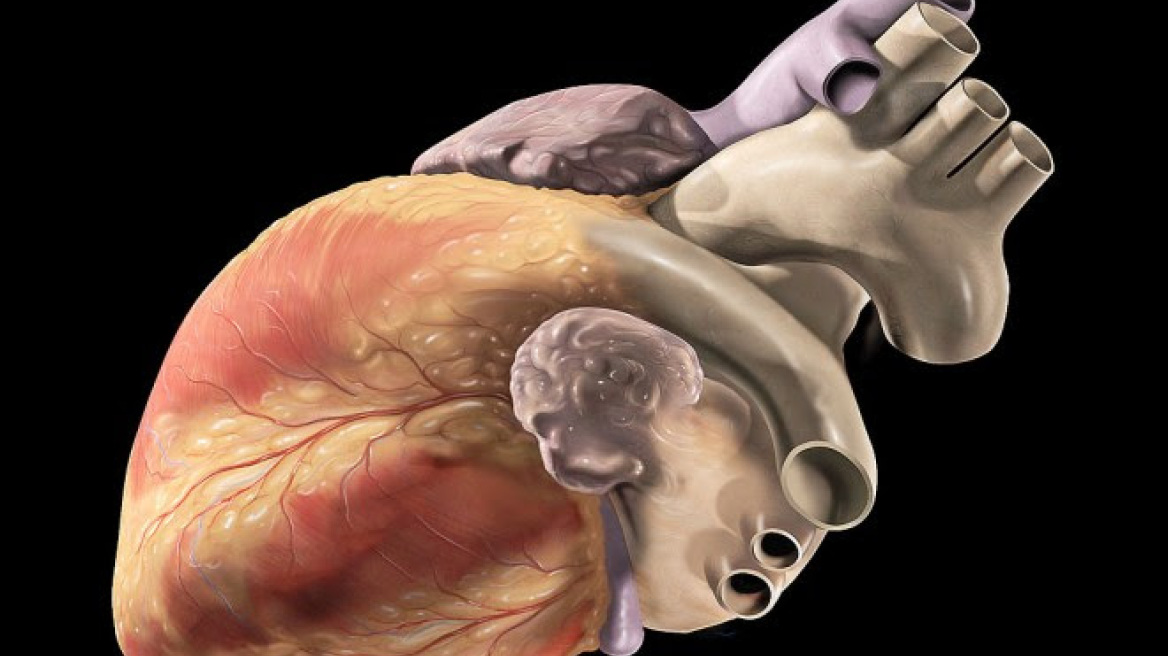

Γνωρίζετε ποια είναι η πραγματική ηλικία της καρδιάς σας; Aυτήν είναι συνάρτηση πολλών παραγόντων, όπως το βάρος, το ύψος, η αρτηριακή πίεση και η χοληστερόλη.